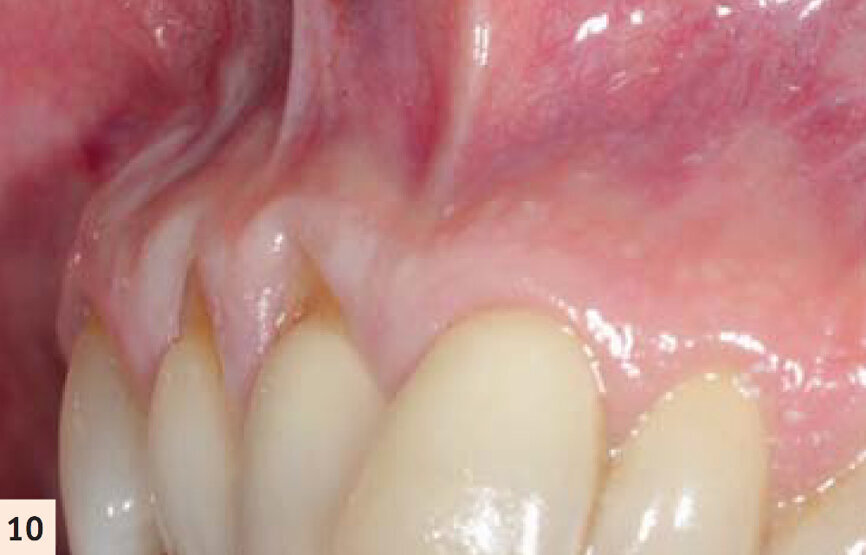

figure 10 : Vues pré- et postop (2 ans). Noter l’augmentation tridimensionnelle de la zone de tissu kératinisé et attaché, ayant pour résultat la restauration de la perte d’attachement et la correction de la

déformation gingivale en hauteur et en largueur.